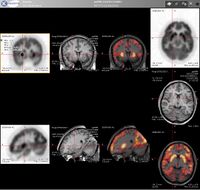

التصوير المقطعي بالإصدار البوزيتروني إنگليزية: Positron Emission Tomography أو PET تقنية تصوير في الطب النووي تسفر عن معطيات وصور ثلاثية الأبعاد لمجرى مختلف العمليات الوظيفية في الجسم. ويعمل الجهاز المصوّر على أساس اكتشاف أزواج من أشعة غاما المنبثفة بشكل غير مباشر عن نظير مشع مصدر للبوزيترونات (قائفة مشعة)، والتي يتم إدخالها إلى الجسم بعد أن ترتبط بجزيء فعال حيويًا). من ثم، يتم استبناء الصورة ثلاثية الأبعاد من الإسقاطات بشكل محوسب. في الآونة الأخيرة، أصبحت تستعمل أجهزة تسهل الاستبناء بواسطة استعمال التصوير الطبقي المحوسب بواسطة الأشعة السينية (أشعة إكس) والذي يتم إجراءه في نفس جهاز التصوير بالإصدار البوزيتروني وفي نفس الوقت.

إذا كان الجزيء الفعال حيويًا الذي يرتبط بالقائفة هو جزيء الـFDG (إحدى مضاهئات الجلوكوز)، فإنّ تصوير تركيز القائفة يعطي قياسًا للفعالية الأيضية في الجسم من منظار قدرة النسيج المحليّة على قبط الجلوكوز. مع أنّ استمعال هذه القائفة بات شائعًا في التصوير المقطعي بالإصدار البوزيتروني، فهنالك العديد من القائفات الأخرى التي قد تعطينا معلومات عن تراكيز جزيئات مختلفة في الجسم.

وفق الإحصائيات الملتقطة من تزامن اصطدام أزواج فوتونات بالمفراس، بالإمكان حل هيئة معادلات لكمية فعالية القائفة المشعة في كل قطعة من النسيج المنشود على طول عدّة خطوط LOR. بهذا الشكل يتم تخطيط النشاط الإشعاعي لكل فوكسل في النسيج. الصورة النهائية تظهر جميع الأنسجة التي تركزت فيها القائفة المشعة، وهي صورة يستطيع أخصائي أشعة أن يقرأها ويستخلص منها الاستنتاجات.